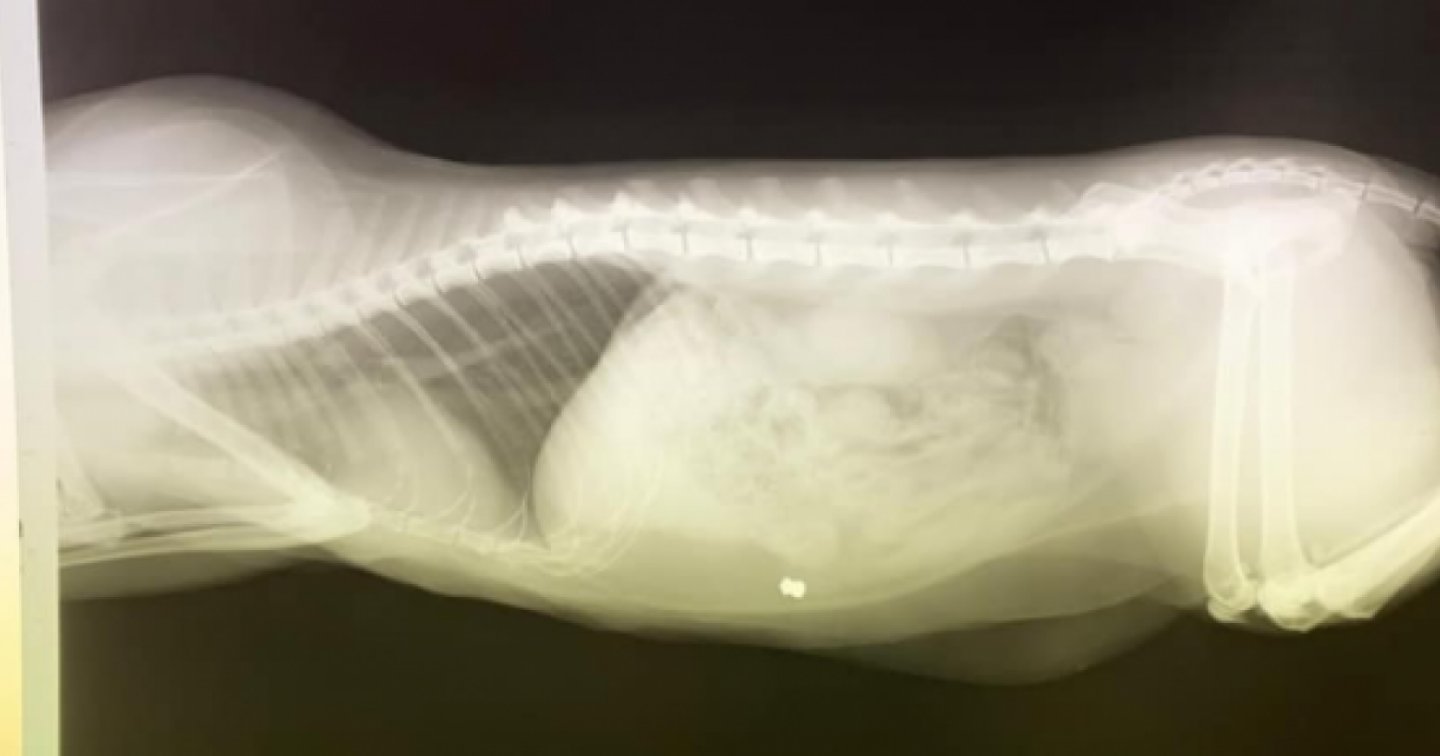

ROBASACCO – "Schifo, siamo nel 2020 e c'è gente che si diverte – probabilmente per gioco – a sparare agli animali". Inizia così il post Facebook con cui Adela denuncia quanto accaduto la prima notte dell'anno al suo gatto a Robasacco. "In questo caso – scrive postando la radiografia del corpo del gattino – è coinvolto il mio gatto. Giuro che se becco chi è stato, non so cosa potrei fargli. Sei un bastardo".